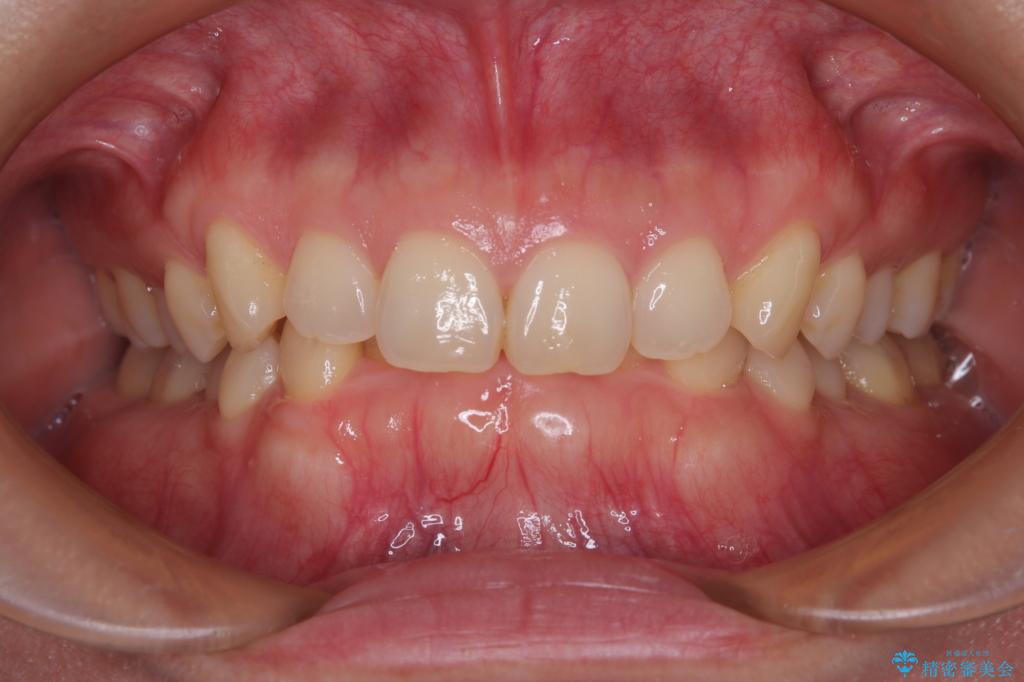

- 下顎前歯が完全に隠れてしまっていることを気にして来院された患者様です。

下顎の臼歯が手前に傾斜していることで咬み合わせが深くなってしまい、下顎前歯が見えないほどに上顎前歯が覆い被さっている状態でした。

下顎臼歯を起き上がらせるためにユーティリティーアーチを使用し、一気に深い咬み合わせを改善することができました。